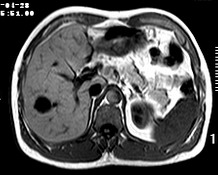

标题: CT19720:肝右叶血管瘤。肝左叶内侧段病灶考虑什么? [打印本页]

标题: CT19720:肝右叶血管瘤。肝左叶内侧段病灶考虑什么?

男,48岁,肝区不适月余,伴隐痛。

支持右叶血管瘤,左叶病灶考虑肝腺瘤。

1)不排除肝左叶肝癌。2)肝右叶血管瘤。

肝左叶炎性病变,肝癌待排。2)肝右叶血管瘤。

1.肝右叶血管瘤;2.肝左叶炎性假瘤?肝癌?建议穿刺活检.

右叶病灶典型,左叶病变慢性炎块

1、肝右叶血管瘤(典型)。

2、肝左叶病灶,强化不明显,疑炎性假瘤,建议结合临床并密切随访。

1、肝左叶炎性病变,肝癌待排。

2、肝右叶血管瘤。

肝左叶脓肿,肝癌待排。2)肝右叶血管瘤